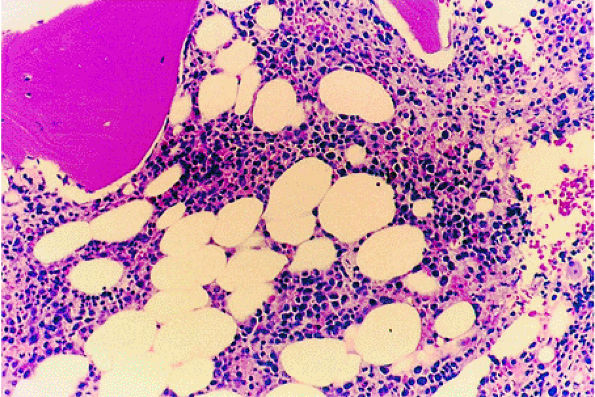

![]() |

FIGURE 13.23 ● Idiopathic neutropenia after colony-stimulating factor therapy. Immature myeloid precursors can be seen in the interstitial space (H & E; original magnification × 400).